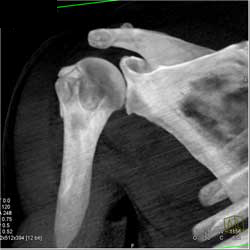

Diagnosis

Bleed in Thigh